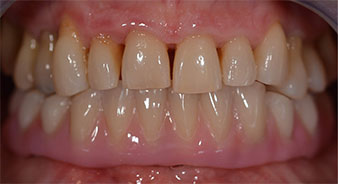

Пациентката е 64-годишна жена с частично обеззъбяване на зъби 38, 33 и 43 и частична долночелюстна протеза (Фиг. 1 и 2).

След изчакване на необходимото време за осеоинтеграция, финалният отпечатък на имплантите е свален и следователно е изработена финалната протеза (Фиг. 19 и 20). В този момент, лекарят по дентална медицина и пациентът могат да обсъдят дали да използват керамични или пластмасови фасети и циркониева или метална рамка. В този случай, екипът на д-р Паску избира пластмасови фасети, имайки предвид неясната прогноза относно частичното обеззъбяване в челюстта и фактът, че зъб 24 е прорастнал. Този вид протеза обикновено е по-лесна за адаптиране и впоследствие може да бъде променяна спрямо новата ситуация в челюстта.